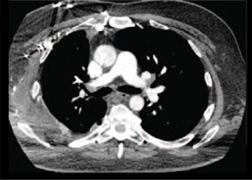

P3T PA (pulmonary angiography), from Medrad, is a personalized contrast-dosing software that increases the percentage of diagnostic-quality CT pulmonary angiography (CTPA) studies to rule out pulmonary embolism (PE).

Researchers have concluded that suboptimal CTPA interpretations to rule out PE can substantially impact healthcare resource utilization and increase healthcare costs. With 30 percent of their CTPA studies showing suboptimal results, these patients were subjected to additional imaging studies and/or received medical therapy. Some patients were admitted to the hospital for further PE diagnosis considerations. None of the additional treatments or imaging modalities yielded a diagnosis of PE.